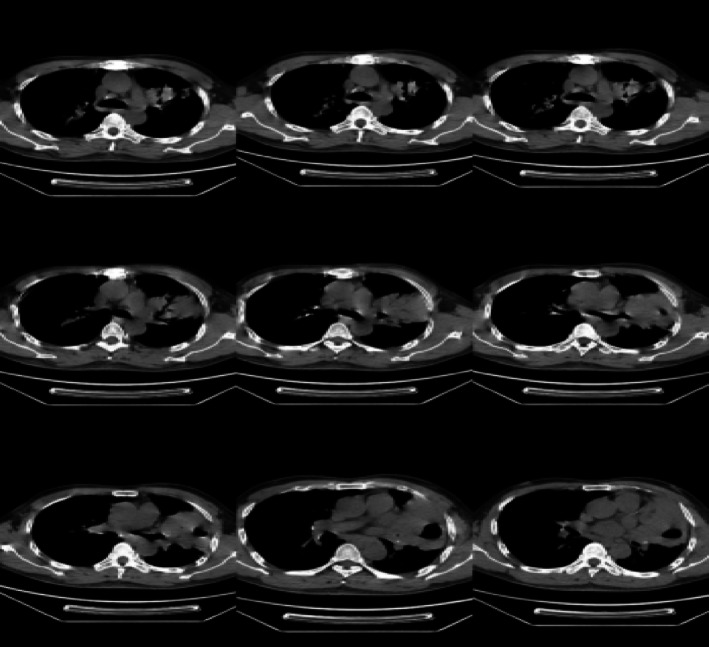

支气管粘膜相关淋巴组织是罕见的粘膜相关淋巴组织(MALT)淋巴瘤的发生部位。由于缺乏明显的临床征象和影像学特征,它经常被误诊和漏诊。在多家三级医院接受肺部感染或肺结核治疗失败后,我们报告了一位男性患者,他的左上肺有一个实性病变长达18年。患者最终在我院采用Jiang技术行CT引导下经皮肺活检(即在常规CT引导的基础上采用激光辅助引导系统)诊断为肺部MALT淋巴瘤。当肺内病变难以用一般肺部疾病来解释时,扩展一个人的视野,综合肺外体征,并努力获得高质量活检标本是至关重要的。

Bronchial mucosa-associated lymphoid tissue is the site of the uncommon malignancy known as mucosa-associated lymphoid tissue (MALT) lymphoma. Due to its lack of distinct clinical signs and imaging characteristics, it is frequently misdiagnosed and underdiagnosed. After receiving unsuccessful treatment for a lung infection or tuberculosis in multiple tertiary care hospitals, we report a male patient who had a solid lesion in his left upper lung for 18 years. The patient was ultimately diagnosed with pulmonary MALT lymphoma at our hospital through a CT-guided percutaneous lung biopsy using the Jiang technique (i.e., employing a laser-assisted guidance system in addition to the conventional CT guidance). It is vital to extend one's perspective, synthesise extrapulmonary signs, and work toward the conditions essential to get a high-quality biopsy specimen when an intrapulmonary lesion is hard to explain by general lung illnesses.